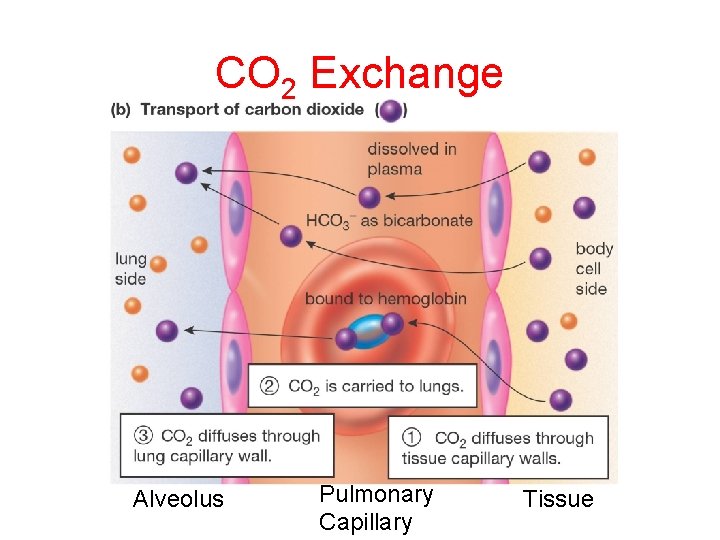

CO 2 Exchange Alveolus Pulmonary Capillary Tissue